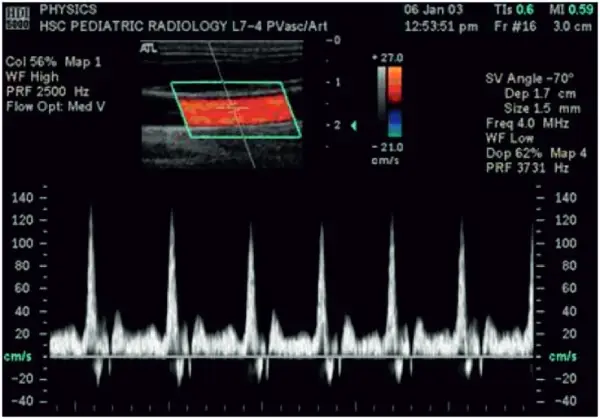

Doppler Sonography

Sonography can be enhanced with Doppler measurements, which employ the Doppler effect to assess whether structures (usually blood) are moving towards or away from the probe, and its relative velocity. By calculating the frequency shift of a particular sample volume, for example a jet of blood flow over a heart valve, its speed and direction can be determined and visualised. This is particularly useful in cardiovascular studies (sonography of the vasculature system and heart) and essential in many areas such as determining reverse blood flow in the liver vasculature in portal hypertension. The Doppler information is displayed graphically using spectral Doppler, or as an image using color Doppler (directional Doppler) or power Doppler (non directional Doppler). This Doppler shift falls in the audible range and is often presented audibly using stereo speakers: this produces a very distinctive, although synthetic, pulsing sound.